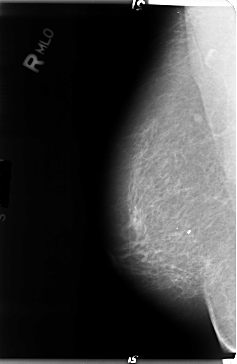

Digital Database for Screening Mammography

Volume: cancer_01 Case: B-3045-1

B_3045_1.RIGHT_MLO

RIGHT_MLO LINES 4720 PIXELS_PER_LINE 3080 BITS_PER_PIXEL 12 RESOLUTION 50 NON_OVERLAY